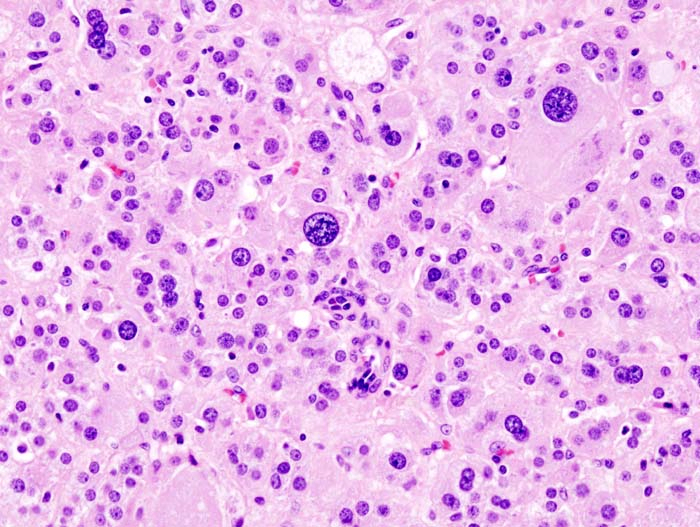

(2) 조직학적 소견

다각형 또는 방추형의 chromaffin cells(=chief cells)가 sustentacular cell에 둘러싸여 혈관 네트워크가 풍부하게 분포하는 작은 둥지/폐포 모양의 구조인 zellballen 형성

신경내분비종양의 전형적인 소견인 finely granular한 세포질과 salt-and-pepper pattern의 chromatin을 보유한 둥글거나 타원형의 핵이 관찰됨

전자현미경 소견으로 electron-dense secretory granule이 관찰됨

Chromogranin, Synaptophysin, S-100 양성

Pheochromocytoma, Wikipedia Commons